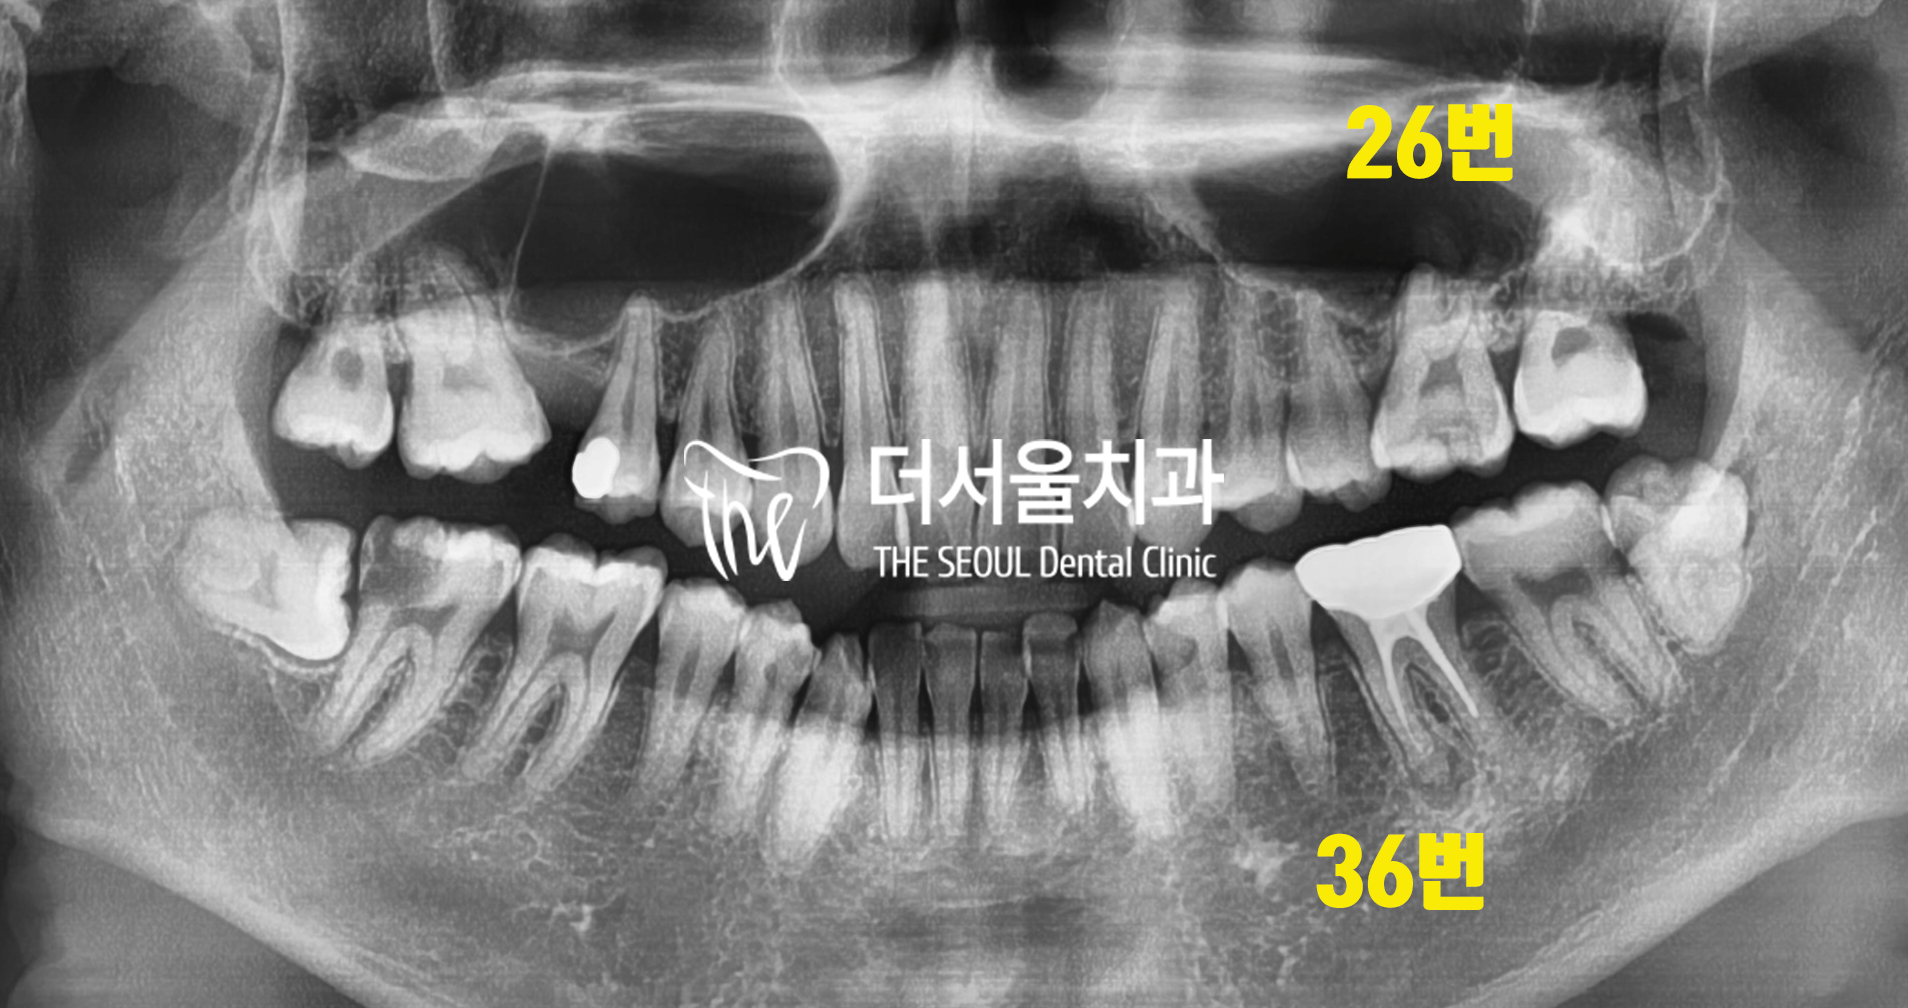

반갑습니다, 여러분! 더서울치과 박현준 원장입니다. 오늘 여러분들께 소개해 드릴 케이스는 제목 그대로, 아말감 밑으로 생긴 이차충치 에 대한 진료